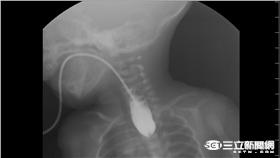

嬰喝水總是嗆到 竟是先天性食道閉鎖

爸媽注意!一名35週早產的女嬰,出現喝水嗆到、口中分...